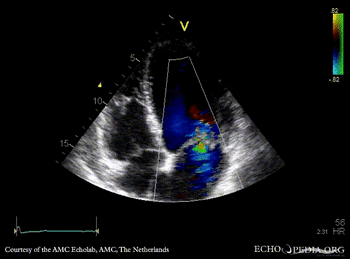

| A3CH with Color Doppler, moderate late systolic mitral regurgitation